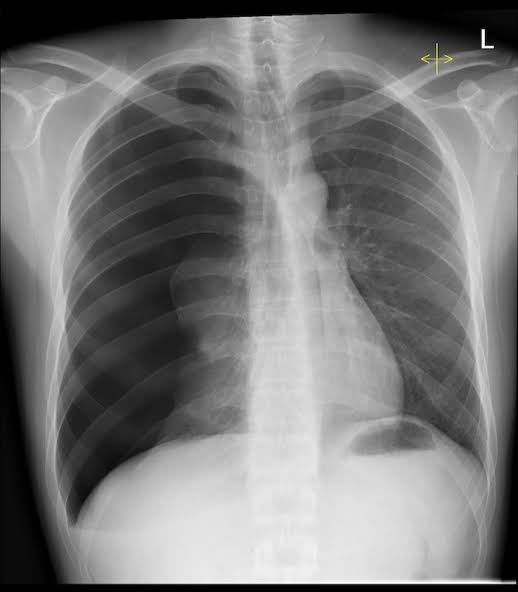

Daya rusak rokok elektronik, yang baru beken belum ada dua dekade, cukup berat ternyata ya. Sa menangani beberapa pasien paru kolaps, sebagai atelektasis atau pneumotoraks, yang usia muda dan merupakan user selama ± tiga bulan pemakaian.

Blom slesai. Kek mana itu atelektasis dan pneumotoraks? Atelektasis artinya paru nguncup krn udara gk bs keluar masuk, sementara paru cenderung kisut. Rokok-el bikin radang saluran napas & ada produksi dahak. Klo berlangsung terus menerus, saluran napas jd rusak & nyumbet.

Lalu apa pulak pneumotoraks? Karena akumulasi partikel kecil yg dihiRup dari rokok-el merusak struktur paru, terjadi cedera tingkat mikro. Bila berlanjut terus, pinggiRan paru bisa robek & udara kejebak di rongga dada, gk bisa keluar. Musti ditoblos chest tube.

Gejala deduanya hampiR sama sih. Ada sesak dan batuk. Sesak pneumotoraks diRasa secara cepat makin berat, kalau atelektasis bervariasi tergantung derajat ketertutupan saluran napas. Batuk sebagai kompensasi proses yg terjadi di dalam dada.